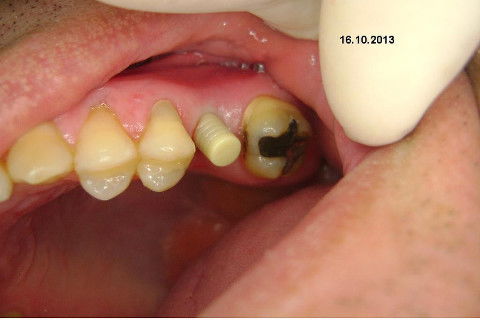

Instalação de um implante em região do 26. Utilizamos um implante cone morse Alvim Neodent 4.3 X 11,5. Foi uma cirurgia muito rápída e minimamente traumática, sem retalho e sutura.

Fotos do caso